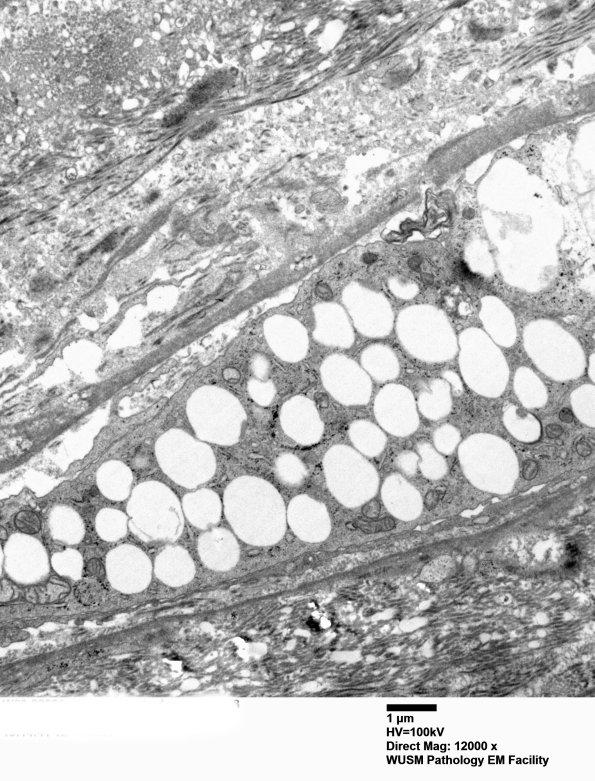

Ultrastructure of the perineurium shows numerous lipid laden macrophages. (electron micrographs)